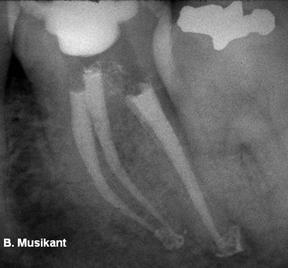

Medicul trebuie sa fie familiar cu variatele cai pe care canalele le pot lua pana la apex. Sistemul este complex, canalele putand sa se ramifice, divide si apoi uni. Weine a clasificat sistemul endodontic in patru clase de baza ce se pot regasii in orice radacina(figura 8).

Figura 8. Clasificarea lui Weine, Castellucci